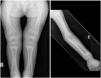

We present the case of a girl aged 2 years and 10 months of African descent brought in for assessment of bone deformities (Fig. 1) and unstable gait, so that the patient required help walking. The relevant findings of the history-taking were exclusive breastfeeding through age 18 months followed by deficient supplementary feeding thereafter, without supplementation with vitamin D in the first year of life and prolonged periods inside the house. The patient exhibited a limp from the moment she started walking and refusal to walk due to pain. Since rickets was suspected, we performed laboratory tests (calcium, 8.4 mg/dL, phosphorus, 2.3 mg/dL, alkaline phosphatase, 2948 U/L; parathyroid hormone, 972.9 pg/mL, 25-hydroxyvitamin D < 10.8 ng/mL) and imaging tests that confirmed severe nutritional rickets (Fig. 2). Treatment started with administration of mega-doses of vitamin D, calcium and alfacalcidol, with subsequent administration of cholecalciferol and dietary changes, with clinical, radiological and laboratory improvement at the time of this writing (Fig. 3). Testing of the mother and brother found deficient vitamin D levels.

Imaging features suggestive of rickets, with significant osteopenia and diaphyseal fracture in both fibulas associated with periosteal reaction. General long bone metaphyseal widening, cupping and fraying. Marked longitudinal widening of the growth plates. Generalised bowing of long bone diaphyses.